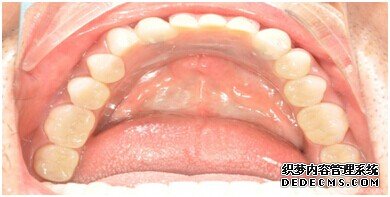

牙齿拍片初步检查

刘女士牙齿拍片初步检查